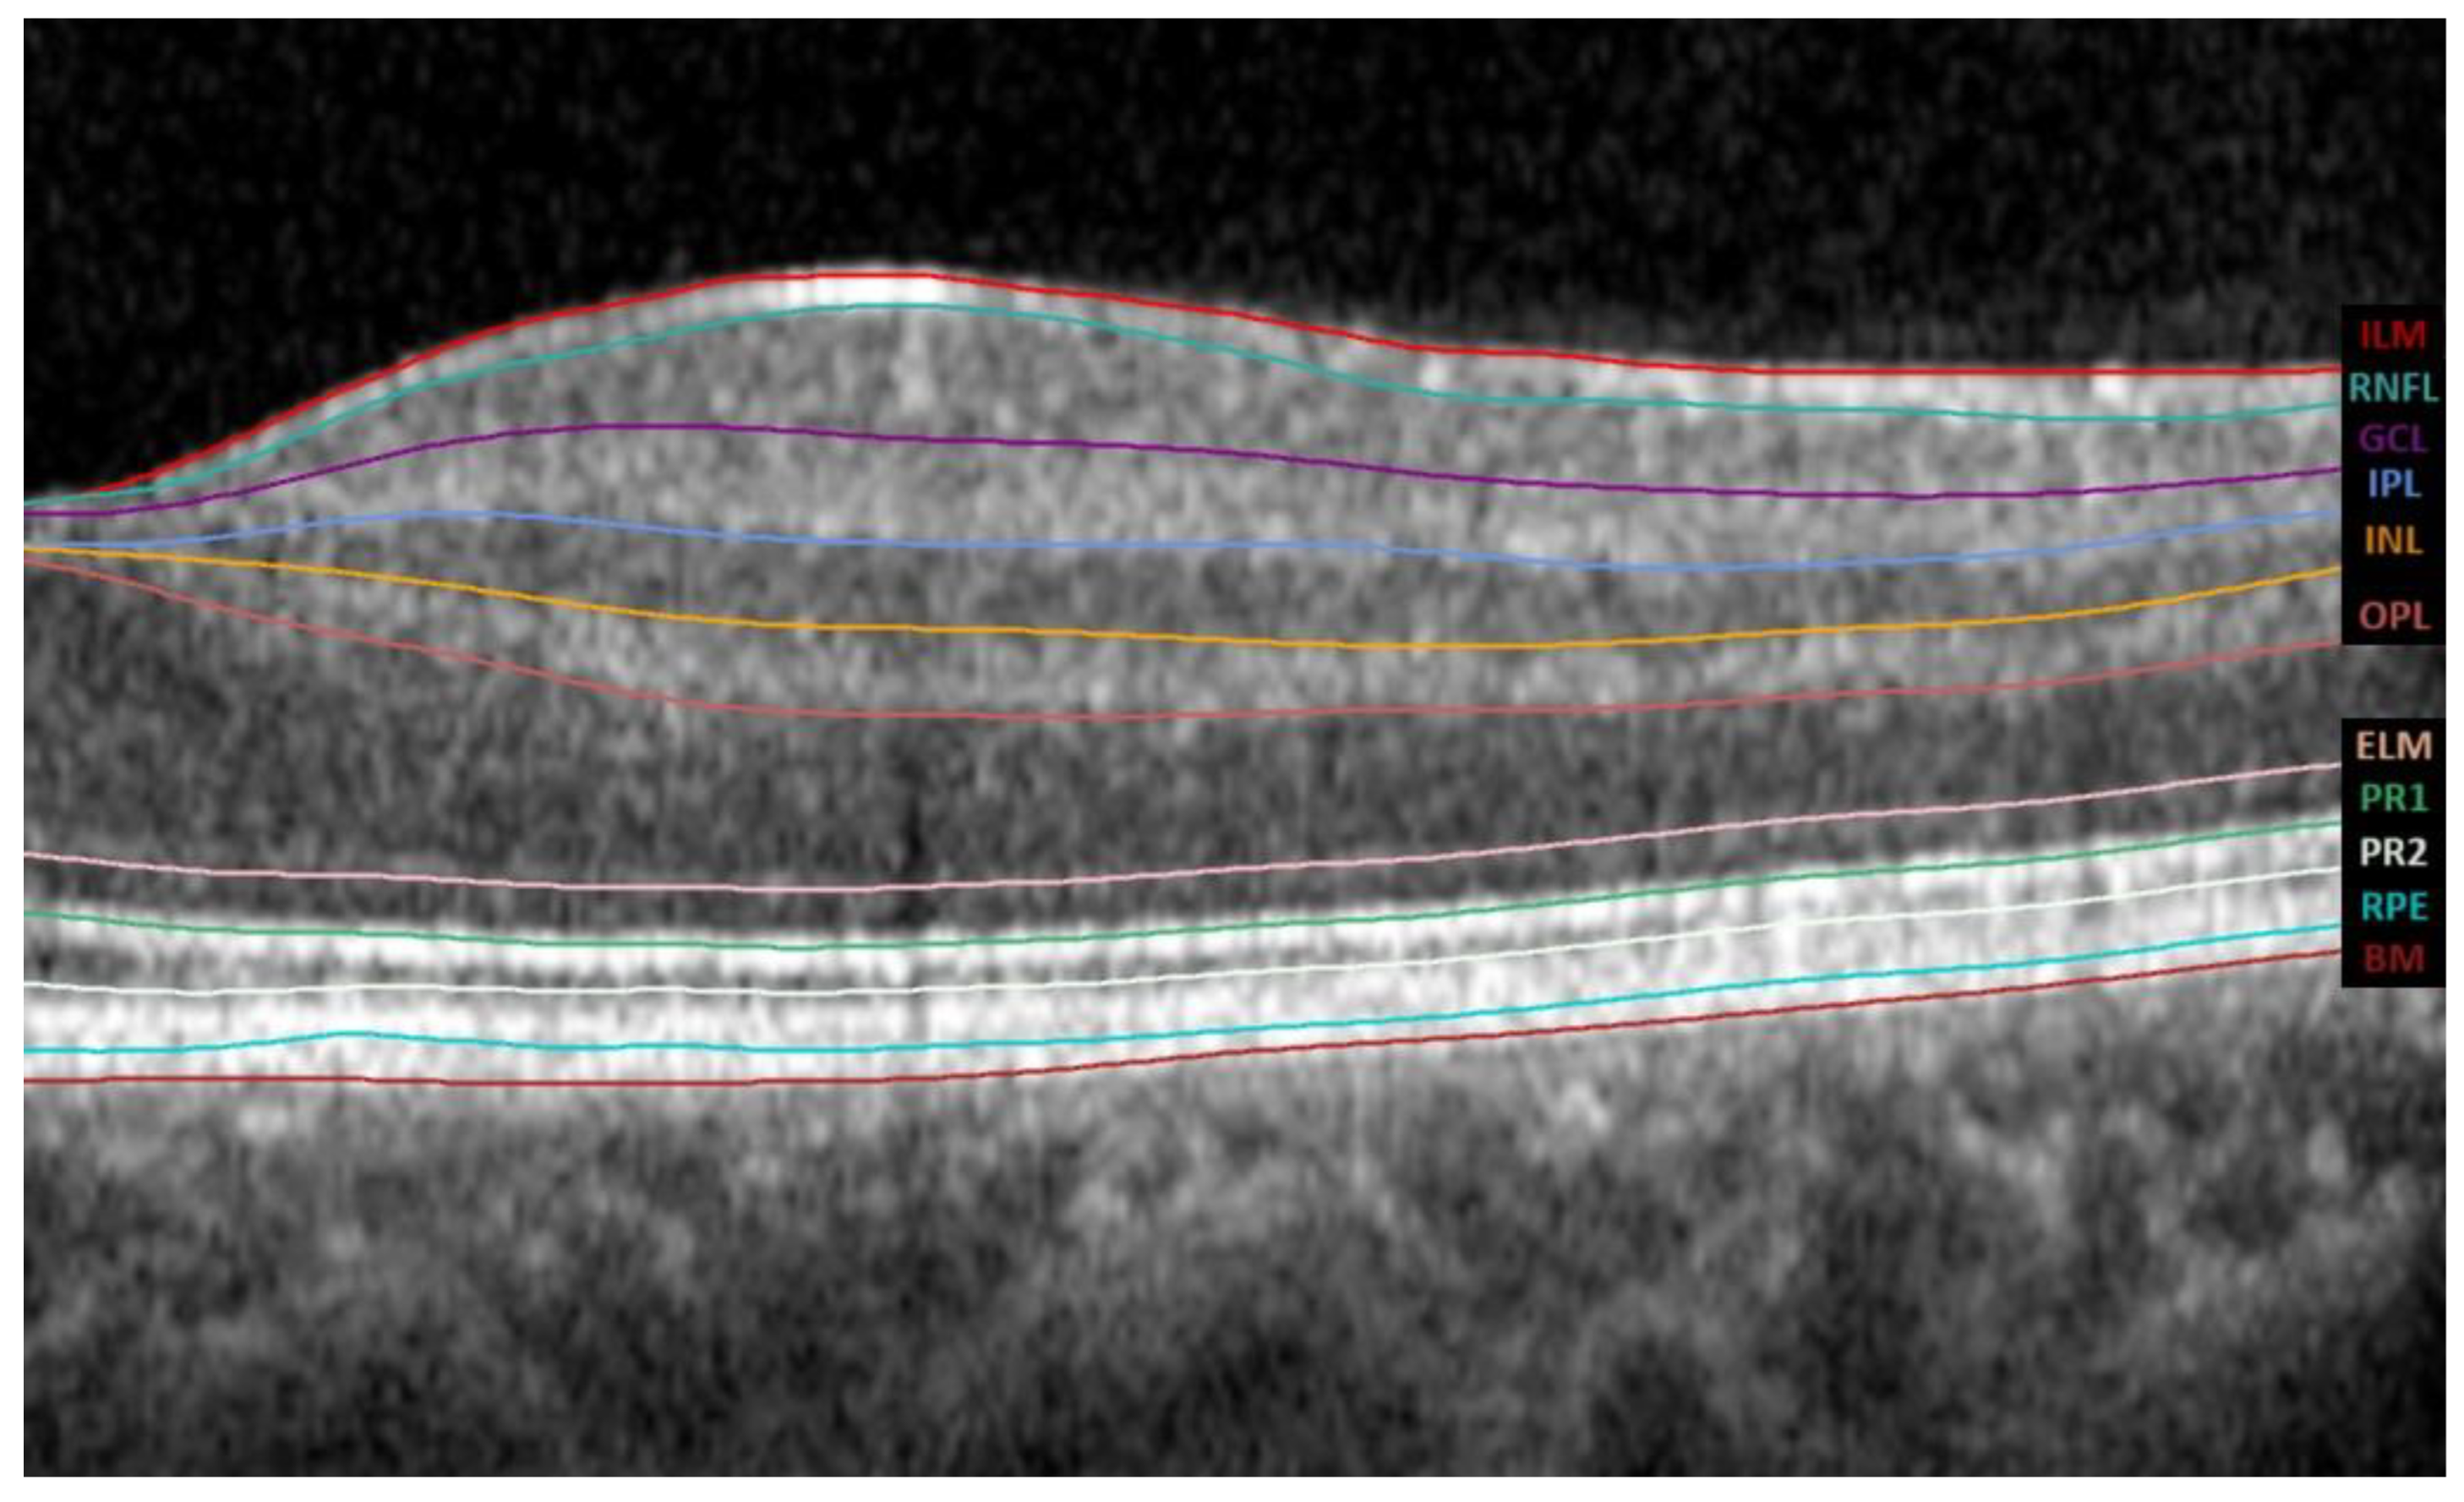

3.3. OCT Thickness Analysis